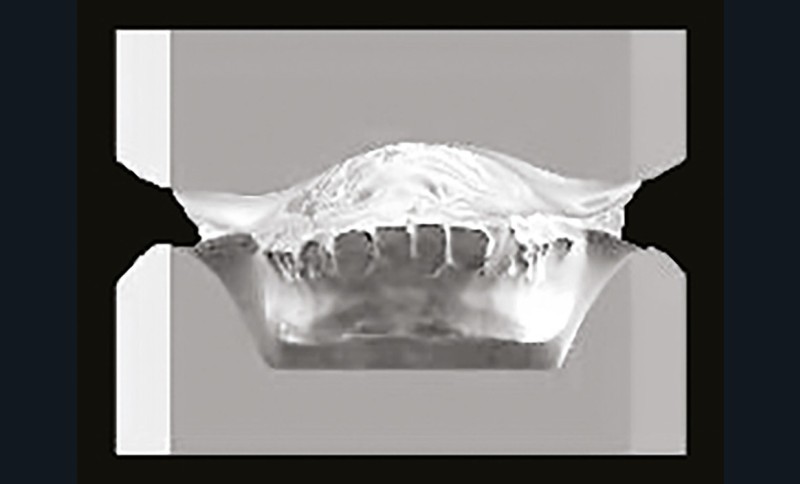

Son profil convexe s’inscrit dans un contexte de classe II squelettique par rétrognathie mandibulaire normodivergente sur un schéma de Classe II/2 avec supraclusion et encombrement modéré (fig. 1 à 7).

La formule dentaire est complète, avec un léger retard d’évolution des deuxièmes molaires (fig. 8).